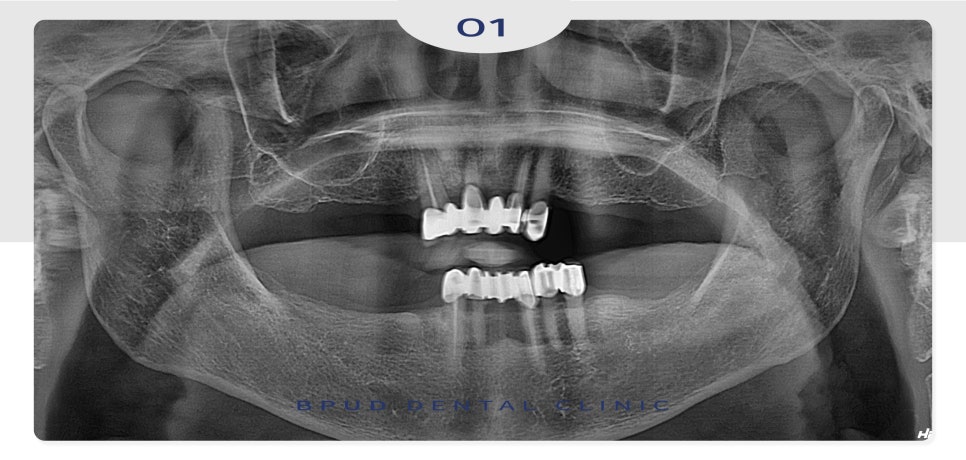

23.03.25

오늘은 오랜 기간 위, 아래 틀니를

사용하시다가 너무 불편하셔서

지인분의 소개를 통해 치료 상담을 위해

부평치과 부평유디치과에 내원해 주신

환자분을 소개해 드리려고 합니다.

환자분께서는 예산 문제로 비용은 줄이면서

틀니는 너무 불편하셔서 원하지 않으신다는

말씀을 해주셨는데요.

적은 개수의 임플란트 식립으로

비용은 줄이고 만족도를 높일 수 있는 방법을

선택하도록 하였습니다.